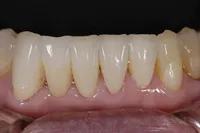

■治療前:生まれつき下顎左右前歯がなく隙間がある

■治療後:矯正治療後、下顎左右3番の2本にインプラント治療

| 主訴 | 生まれつき歯がなく隙間があり、審美障害・咀嚼機能障害がある |

| 治療方法 | インプラント治療 + 矯正治療 |

| 治療期間 | インプラント治療 約6ヶ月 |

| 通院回数等 | インプラント治療 約6回 |

| 費用 | 約94万円(税込) |

| リスク・副作用 | 術後の腫れ・痛み |